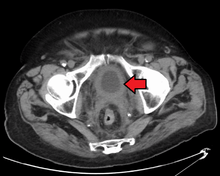

|

Transitional cell carcinoma of the bladder. The white in the bladder is contrast. | |

Bladder cancer is any of several types of cancer arising from the epithelial lining (i.e., the urothelium) of the urinary bladder. Rarely the bladder is involved by non-epithelial cancers, such as lymphoma or sarcoma, but these are not ordinarily included in the colloquial term "bladder cancer." It is a disease in which abnormal cells multiply without control in the bladder.[1]

The most common type of bladder cancer recapitulates the normal histology of the urothelium and is known as transitional cell carcinoma or more properly urothelial cell carcinoma. Five-year survival rates in the United States are around 77%.[2]